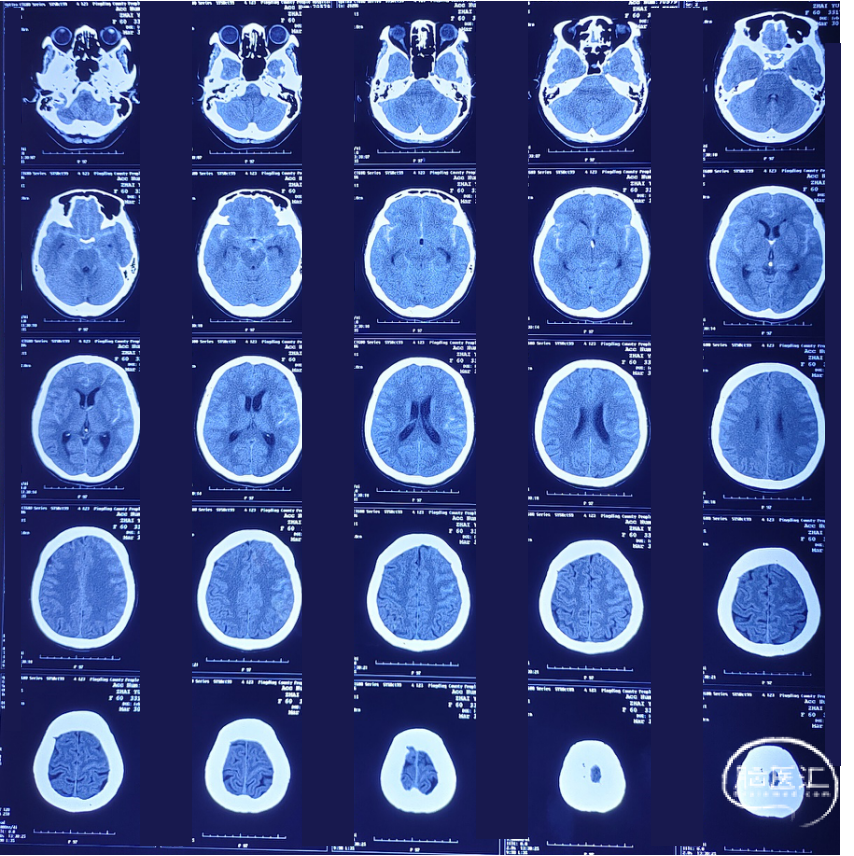

辅助检查:颅脑CT检查提示蛛网膜下腔出血。

术前CT

术后2天CT

术后13天CT